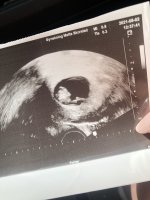

hjertet banket og vi fikk til og med et lite hopp. Målte helt riktig til hvor langt jeg var